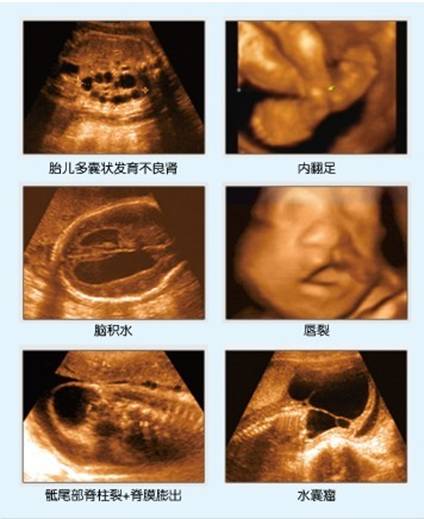

四维彩超适用于:心脏、肝、胆、脾、肾、胰腺、妇产科、外周血管、表浅器官(如眼球、甲状腺、乳腺、阴囊等)软组织各种疾病的检查。尤其在妇产科方面:对胎儿进行超声检查能即时地观察胎儿在子宫内的动态运动,立体显示胎儿的颜色、面、各器官的发育情况,甚至胎儿在母体里的状态也可以观察到,是准妈妈们的4D影院;除了分析胎儿的发育情况、评价多胞胎或高危妊娠外,四维技术还可以应用于胎儿异常(1.胎儿畸形:如唇裂、部分腭裂、骨骼发育异常、心血管畸形等;2.神经系统:无脑儿、脑积水、小头畸形、脊柱裂及脑脊膜膨出;3.消化系统:脐部肠膨出、内脏外翻、肠道闭锁及巨结肠等)、子宫的结构异常、胎盘异常、胎盘定位、子宫异常的出血、异位妊娠和其它的异常妊娠、卵巢的肿瘤和纤维瘤、子宫肌瘤等多项诊断。

利用四维彩超看到的异常胎儿